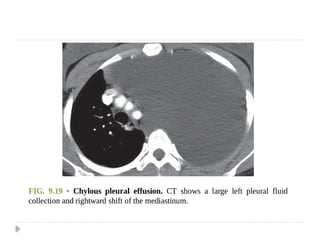

 Chylothorax:

 A chylothorax contains fluid that is largely chyle (lymph of

intestinal origin).

 Because chyle usually contains suspended fat in the form of

chylomicrons, chylothorax fluid may be milky.

 Three main mechanisms account for chyle collections in the

pleural space: (i) leakage from a discrete rupture of the thoracic

duct or a large lymphatic vessel

(ii) a general oozing from pleural lymphatics,

(iii) passage of chylous ascites through the diaphragm

 Approximately 50% of chylothoraces are of neoplastic origin

 25% are traumatic,

 15% are idiopathic

 Lymphomas make up about 75% of the neoplastic lesions , and

chylothorax can be the initial feature of lymphomas